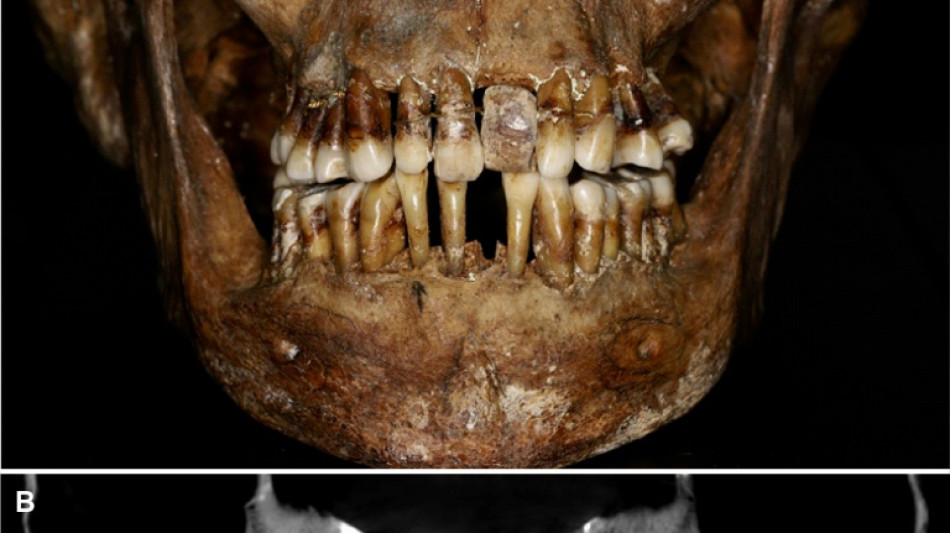

La dentition d'une aristocrate du XVIIe siècle comme marqueur social / Photo: © INRAP/AFP

La sépulture d'Anne d'Alègre, morte en 1619 à l'âge de 54 ans, avait été déterrée lors d'une fouille au château de Laval, en 1988. Embaumé dans un cercueil de plomb, le squelette était particulièrement bien conservé, sa dentition aussi.

Plus de trente ans après, une équipe comprenant des archéologues et des dentistes dévoile qu'Anne d'Alègre était atteinte d'une maladie parodontale qui provoque le déchaussement progressif des dents, selon une étude parue cette semaine dans Journal of Archeological Science.

Les images radiologiques par "Cone Beam", un scanner en 3D, montrent que la patiente portait une prothèse dentaire remplaçant une incisive, soutenue par des fils d'or, ainsi qu'une ligature de contention sur des pré-molaires.

Des examens en macroscopie ont déterminé que cette prothèse était en ivoire d'éléphant, écartant la piste de l'ivoire de dents d'hippopotame, également utilisé à l'époque.

A long terme, ce traitement, ainsi que les "multiples resserrages nécessaires, ont entraîné l'instabilité des dents voisines", détaille l'Inrap.